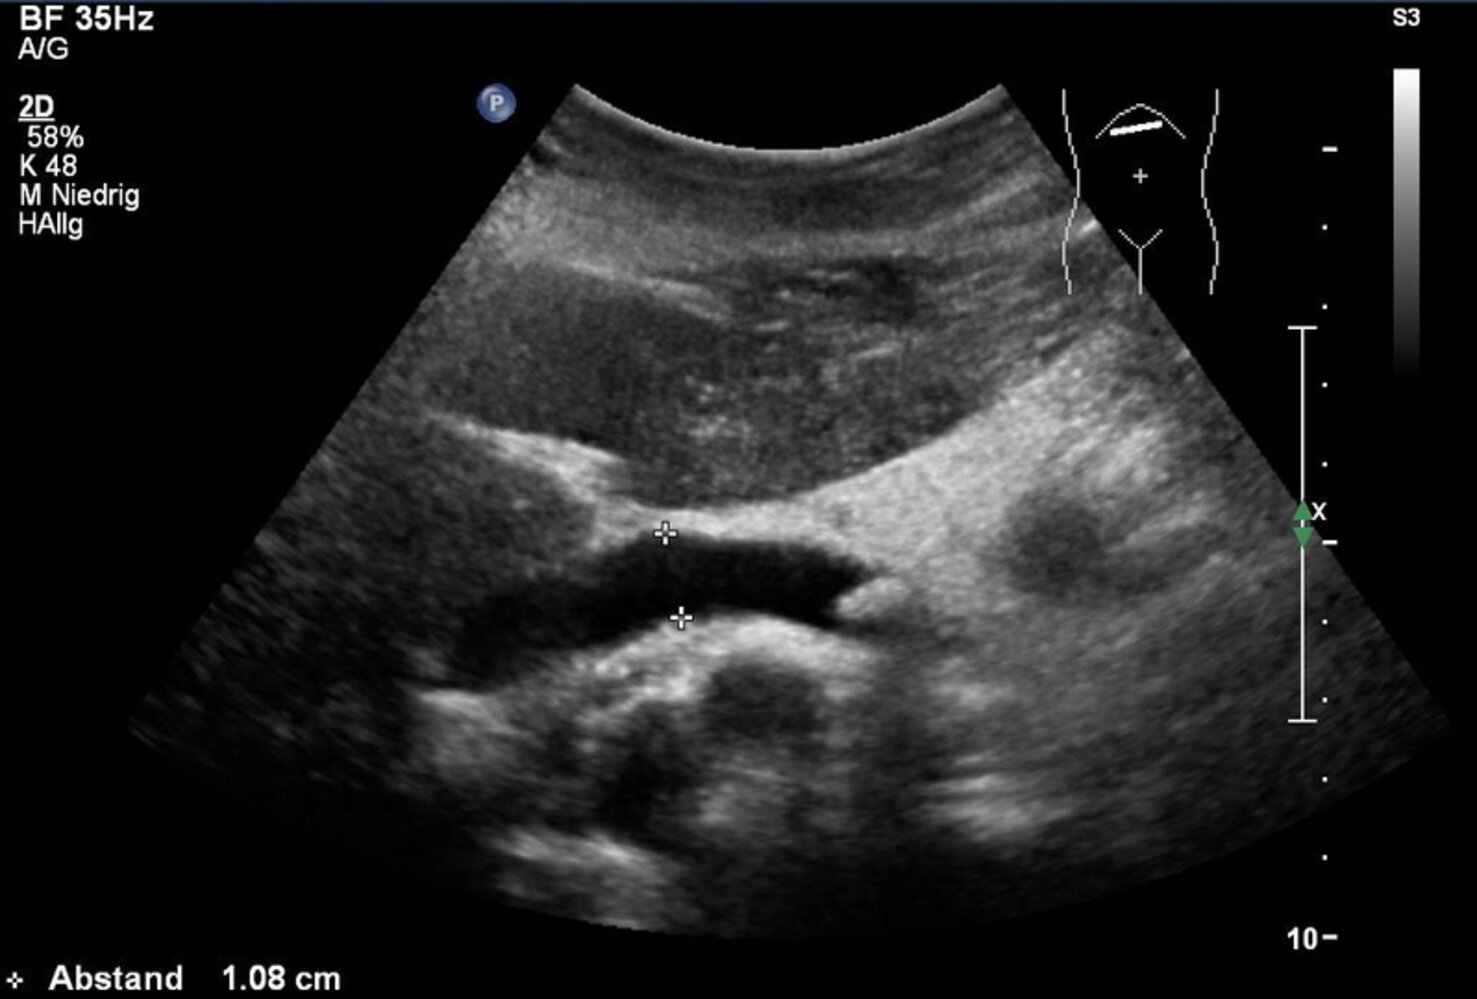

RUQultrasound

• Indication: : preferred first-line imaging modality in patients presenting with suspected cholangitis [8][11][12]

• Supportive findings

• Dilated common bile duct: See ''Diagnosis of choledocholithiasis” for details.

• Dilated intrahepatic bile ducts: indicates obstructive cholestasis

• Thickened bile duct walls [13]

• Evidence of underlying etiology, such as:

• Choledocholithiasis: occluding CBD stone with/without cholelithiasis may be visualized [14]

• Biliary stricture: focal narrowing of the bile duct(s), with dilation of the proximal biliary tree

• Biliary tumor: intraluminal mass within the bile duct

RUQultrasound is not sufficiently sensitive to definitively rule out biliary obstruction. Obtain cross-sectional imaging (i.e., CT abdomen or MRCP) in patients with a high pretest probability of acute cholangitis and a negative RUQultrasound. [8]